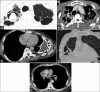

Chest tuberculosis (CTB) is a widespread problem, especially in our country where it is one of the leading causes of mortality. The article reviews the imaging findings in CTB on various modalities. We also attempt to categorize the findings into those definitive for active TB, indeterminate for disease activity, and those indicating healed TB. Though various radiological modalities are widely used in evaluation of such patients, no imaging guidelines exist for the use of these modalities in diagnosis and follow-up. Consequently, imaging is not optimally utilized and patients are often unnecessarily subjected to repeated CT examinations, which is undesirable. Based on the available literature and our experience, we propose certain recommendations delineating the role of imaging in the diagnosis and follow-up of such patients. The authors recognize that this is an evolving field and there may be future revisions depending on emergence of new evidence.